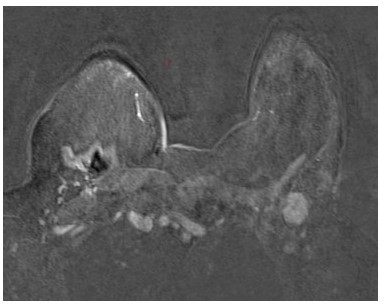

Presentamos el caso de una paciente 53 años, quien consulta refiriendo aumento de volumen en región axilar izquierda de 1 año de evolución. Al examen físico sin evidencia a la palpación de lesiones mamarias, se aprecia en la axila izquierda plastrón ganglionar de 4 cm de diámetro movible, no fijo a estructuras vecinas. En los estudios realizados, como lo son mamografía, eco mamario y resonancia magnética de ambas mamas con gadolinio en marzo 2022, solo se observa, la presencia de lesión de ocupación de espacio en axila izquierda, sugestivo de plastrón ganglionar, sin lesiones subclínicas en las mamas (Figura1,2,3)

La paciente inicia tratamiento neoadyuvante a base de quimioterapia, la culmina el 24 enero 2023, observándose al examen físico: ausencia de lesiones en la mama izquierda, en la axila izquierda, se palpa ganglio axilar, de menor tamaño, de aproximadamente 2 cm, consistencia dura y movible. Se realizan mamografía, ecosonograma mamario, resonancia magnética de ambas mamas con gadolinio 2023 los cuales están dentro de límites normales, y sin evidencia de lesiones en la glándula mamaria.

Los resultados de la ultrasonografía convencional son escasamente alentadores, con un elevado número de falsos positivos y falsos negativos (16). La poca rentabilidad diagnóstica de la mamografía ha elevado el empleo de la resonancia nuclear magnética. Ésta última ha demostrado una alta sensibilidad entorno al 85 %-100 %, pero con una baja especificidad, entorno del 35 %-90 %, oscilando el tamaño de las lesiones que se diagnostican, alrededor de 9 mm y 20 mm, definiendo lesiones malignas mamarias en un 75 % de los casos inicialmente clasificados como cáncer de mama oculto. La resonancia magnética bilateral mamaria, tiene que ser parte de la evaluación de las mujeres con cáncer de mama oculto (19).

Al analizar la literatura, paciente con diagnóstico de cáncer de mama oculto, al realizarse la resonancia magnética con gadolinio, en los 2/3 de los casos dejaron de serlo, debido al hallazgo imagenológico de la lesión primaria en la glándula mamaria. Parece definido en la bibliografía que el valor de la mamografía vs., la resonancia magnética, en la detección del cáncer de mama oculto es bajo con una sensibilidad del 29 % y una especificidad del 73 % (15,16).